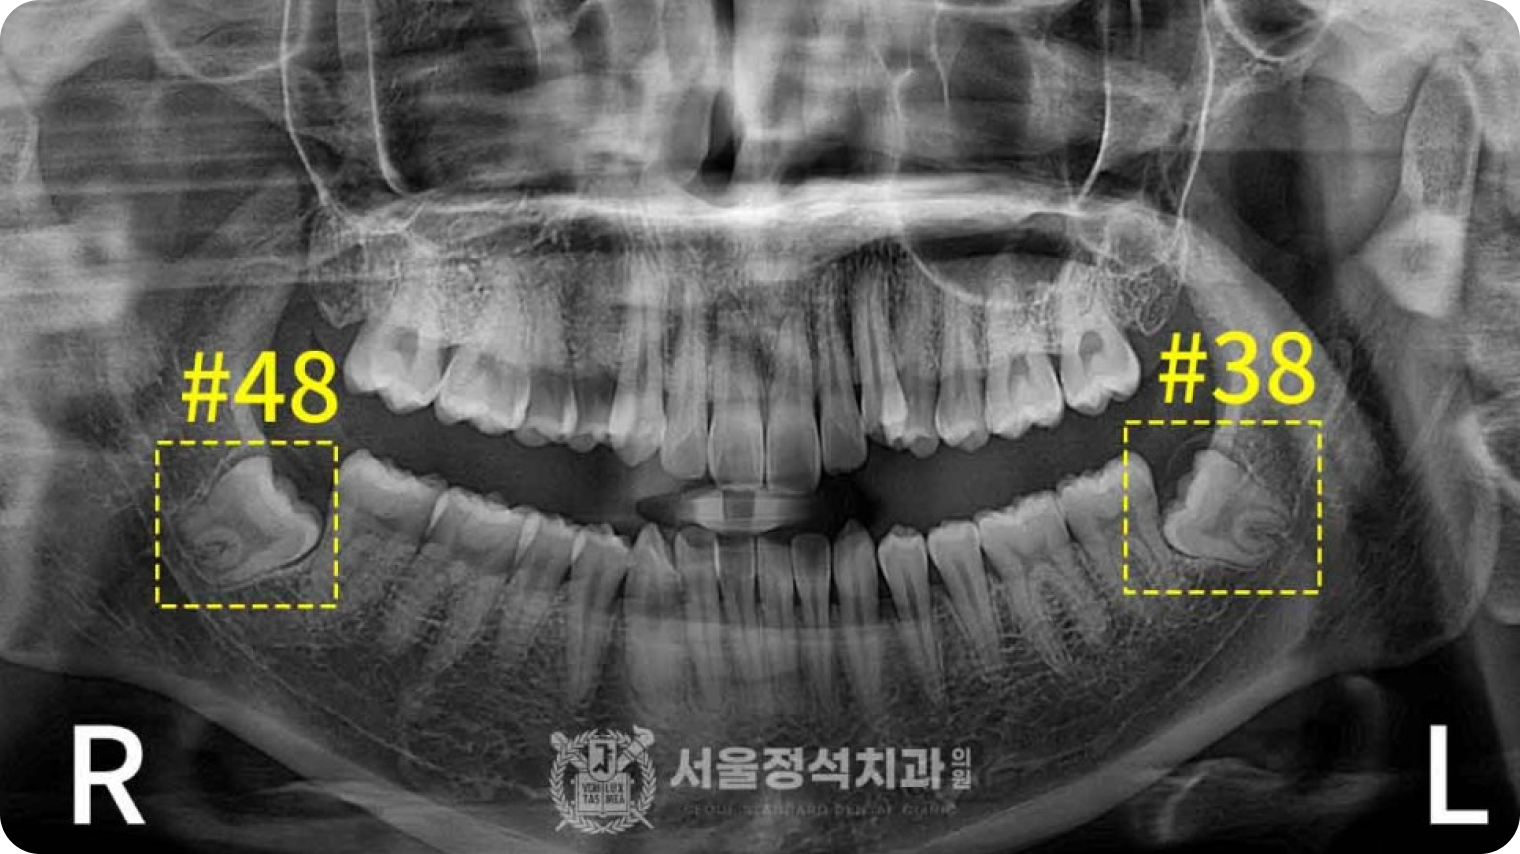

당일 사랑니 발치

당일 사랑니 발치

당일 사랑니 발치

사랑니는 영구치열을 방해하고 관리가 어려워 충치, 염증 등 문제를 일으킵니다. 신경까지 고려하는 당일 사랑니 발치로 빠르고 안전하게 해결합니다.